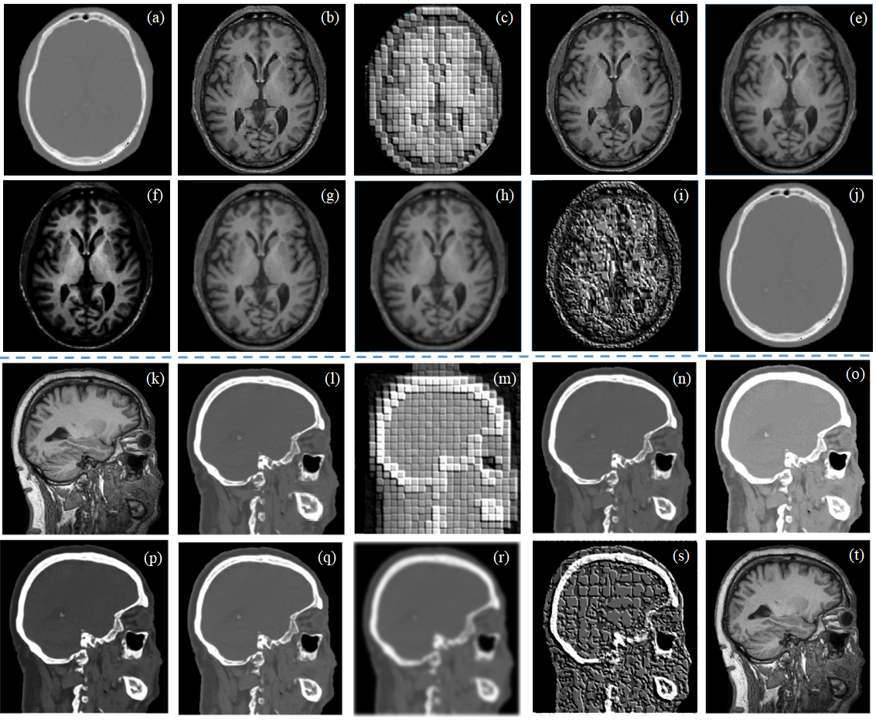

Figure 3: (with ground truth) Qualitative analysis of unpaired CT-MRI-CT translation of real brain images: (a) given CT, (b) translated MRI by baseline CGAN, (c) an unpaired MRI for conditioning; translated MRI when conditioned by: (d) random target image, (e) average target image, (f) sample PDF, (g) 8×8888\times 8 patch, (h) 16×16161616\times 16 patch; (i) back translated CT from (h), (j) ground truth MRI for (a); difference image: (k) between (a)-(j), (l) between (a)-(h).

Fig. 3 displays a qualitative result obtained using the pCCGAN by different conditioning scenarios for unpaired cyclic CT-MRI translation. Fig. 3 (j) shows ground truth MRI. One may observe that the MRI generated by conditioning of 16×16161616\times 16 patches (Fig. 3 (h)) optimally utilizes the cross-neighborhood pixel information and achieves superior translation and restoration. Quantitative and ablation test analysis for 100 test image translations are presented in Table I. This confirms the superiority of proposed approach conditioned with 16×16161616\times 16 concatenated alternate patches with DiL. Further, Fig. 4 (a) to (t) display a few qualitative results for unpaired cyclic CT-MRI-CT and MRI-CT-MRI translation when the ground truth is not present. One may observe from Fig. 4 that the proposed approach performs superior unpaired translation even in the absence of ground truth.